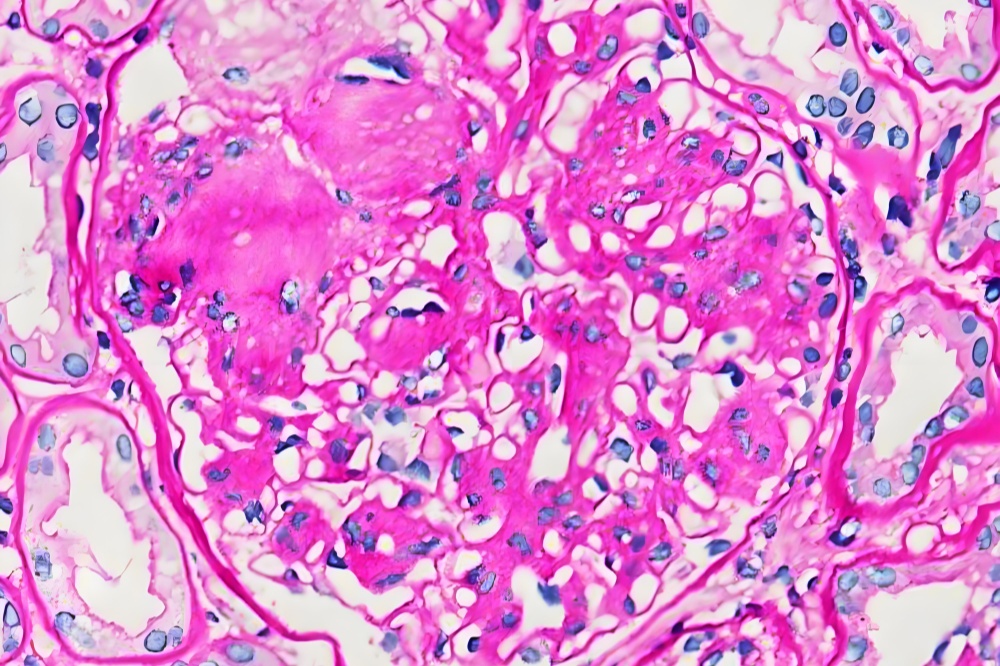

PAS染色(中性粘液和杯状细胞)

PAS(过碘酸-Schiff)染色是一种经典的中性粘液物质与糖原特异性标记技术,通过过碘酸氧化糖类中的乙二醇基团生成醛基,再与Schiff试剂反应形成紫红色沉淀。该技术能清晰显示:杯状细胞分泌的中性粘液(如胃肠道、呼吸道黏膜),糖原储存(如肝细胞、肌细胞),基底膜结构(如肾小球基底膜增厚评估)!

高对比度:紫红色阳性信号与蓝色复染背景形成鲜明对比